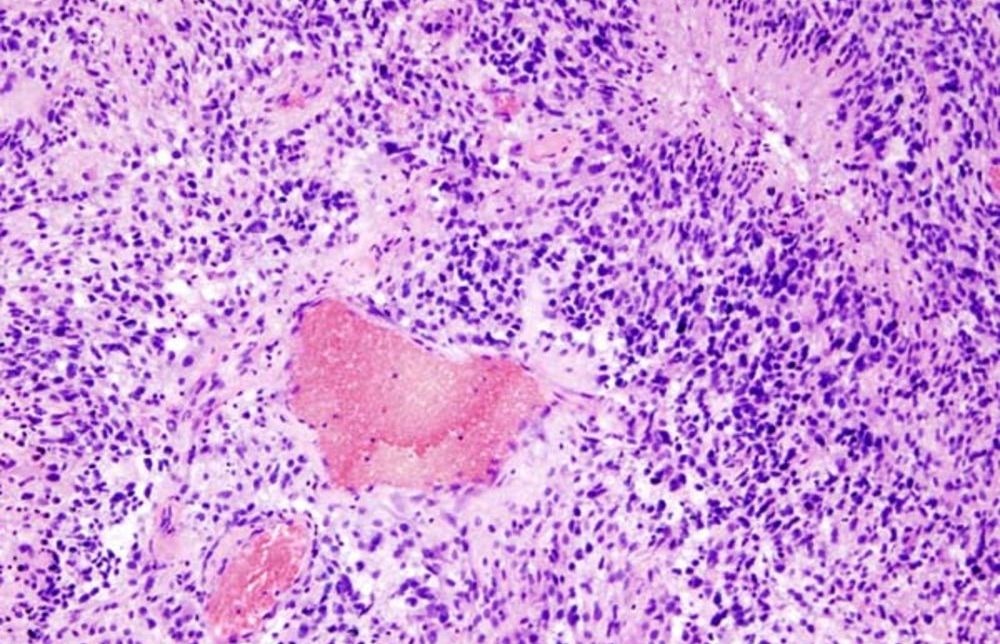

Глиобластому часто называют раком мозга. Заболевание развивается из эпителиальной ткани различных органов.